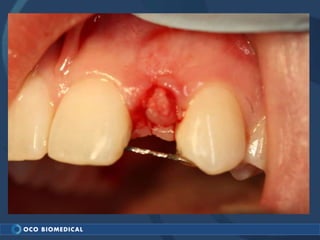

A 3.0mm dental implant was placed to replace congenitally missing maxillary lateral incisors. Dr. Tim Kosinski used a 1.8mm pilot bur and tissue punch to prepare the osteotomy site, then placed the implant by hand and seated it with a torque wrench. After ensuring the implant trajectory was within the restorative envelope, an acrylic coping was placed for temporary fabrication. At the 1 week post-op appointment, excellent soft tissue response and papilla formation were observed, and a final impression was taken to send to the lab for crown fabrication.